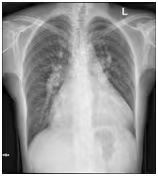

患者女,41岁,发现先天性心脏病7年,加重1月。7年前体检发现先天性心脏病,出现活动后心慌,休息后可缓解,未予重视,1月前上述症状加重,伴体力下降,夜间阵发性呼吸困难。

检查结果示:1、2022.10心脏彩超示:先天性心脏病,Ⅱ孔型房间隔缺损(中央型)房水平分流,动脉导管未闭;2、肿瘤标志物示:糖类抗原125(CA125)331.90 U/ml↑(正常范围0-35 U/ml)。

诊断:房间隔缺损、动脉导管未闭,肺动脉高压,二尖瓣关闭不全,三尖瓣关闭不全,心脏扩大。

医师决定行二尖瓣机械瓣置换术(保留瓣下结构),三尖瓣成形术,房间隔缺损人造补片修补术,动脉导管未闭切段缝合术。术前为排外手术禁忌证,2022.11行PET/CT示:巨大心脏显影,房室各壁心肌代谢明显增高。

术后3个多月后心脏彩超示:先天性心脏病,术后房水平分流消失,动脉水平分流消失,机械表功能正常,三尖瓣功能正常,左、右室收缩功能减低,微少量心包积液。

PET/CT全身显像在先心病方面检查较少[1-2] ,多为感染性心内膜炎和心脏设备感染的运用,PET/CT为患者提供了额外的诊断价值,并改善了病例分类[3]。该病例为先心病PET/CT全身显像巨大心脏显影,形似“花瓣儿”,较为少见。患者术后症状明显得到改善,定期复诊。PET/CT全身显像对先心病患儿具有一定的临床价值。

(图1)先天性心脏病患者(女,41岁)18F-FDG PET/CT显像图。1A.全身最大密度投影图示心脏明显扩大,房室各壁糖代谢明显增高;2B.心脏断层显像示各室壁糖代谢明显增高,SUVmax为11.5;1C.横断面、冠状面、矢状面三个不同层面示心腔明显增大,各室壁糖代谢明显增高。图2同一患者胸片。2A.2022年10月(手术前)胸片:心胸比为0.88;2B.2022年12月(手术后)胸片:心胸比例为0.76。